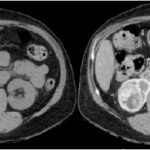

Fase sin contraste o basal

En la exploración renal se debe incluir esta frase dentro del protocolo; la fase proporciona la información inicial de una masa tumoral sospechosa, lo que permite tener un punto de referencia al compararse con las fases post-contraste. Los valores mayores a 12 UH son sospechosos de malignidad; teniendo en cuenta que el CCR es un tumor vascularizado, su atenuación aumenta a 20.

UH o más; si dichos tumores son mayores a 3 cm tienen características más heterogéneas en comparación con los tumores menores a 3 cm, que son más homogéneos.

Las calcificaciones se encuentran hasta en un 30% de los CCR y son más fácilmente visibles durante la fase basal 3-4 (Fig. 1).